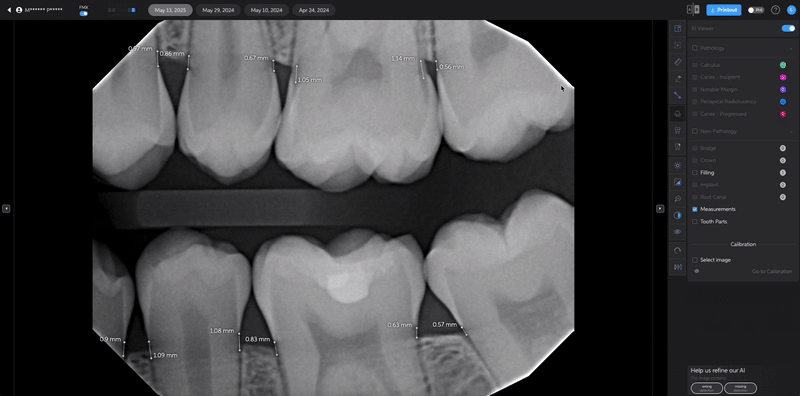

- Restore a Removed Detection

- If you remove a detection by mistake, simply click the eye icon again to restore it.